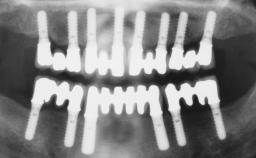

Conventional Loading of Eight Implants in the Maxilla and Final Restoration with a Full-Arch Gold-Ceramic FDP

# of Implants | 8 |

Attachment | One-Piece |